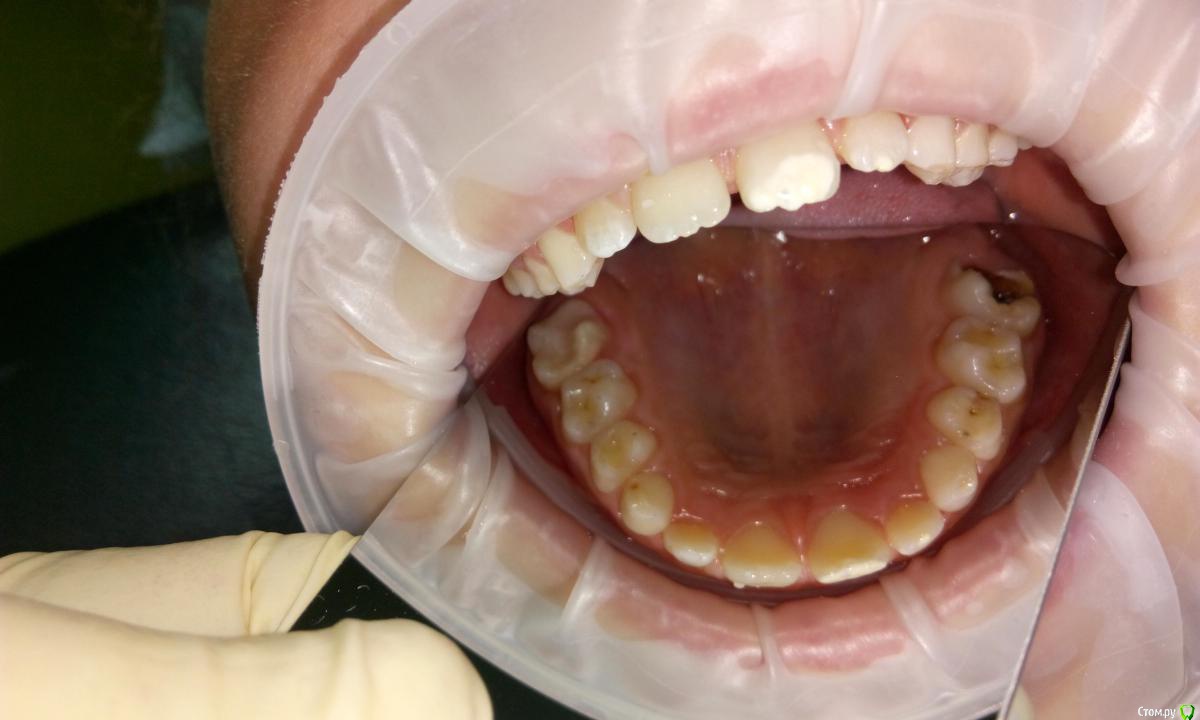

Уважаемые коллеги,обратилась девочка 8 лет на удаление молочного зубика, больше её ничего не беспокоило. Зубик удалил и нашёл ещё много чего интересного. Раньше не приходилось сталкиваться с таким мегаразрушительным кариесом. Да и вообще с чего начать, за что браться не представляю. Помогите пожалуйста. Все пломбы, что найдёте из Vitremerа, кроме той что на 1.6-там Nanopaq.

Зуб 2.6 думаю витально ампутировать, зуб 3.6 возможно тоже, но может обойдетесь МТА на рог пульпы. Остальные в плановом порядке лечить. Думаю, все будет ок)